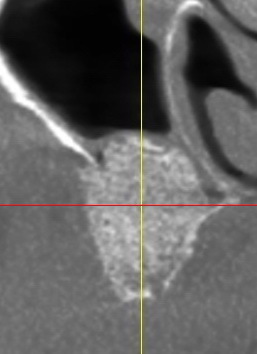

GREFFE DU SINUS: QUELLE GREFFE ?

GREFFE DU SINUS: LE COMBLEMENT SINUSIEN